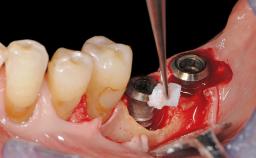

Paolo Casentini and Matteo Chiapasco present a case in which the peri-implant defect was not suitable for a fully regenerative approach. It involves implant removal, use of a CAD/CAM customized titanium mesh in the grafting phase, and placement of new implants. A 62-year-old woman was referred for consultation regarding her implant-supported prosthesis replacing teeth 14 to 16. The patient’s main concern was pain and recurrent swelling in the right posterior maxilla. The patient also reported difficulty and discomfort when brushing the area. The patient reported she had been treated in another country, where she had received three implants in combination with sinus-floor augmentation for the replacement of the posterior maxillary teeth three years earlier. The patient indicated “endodontic complications” to be the reason for the extraction of the teeth.